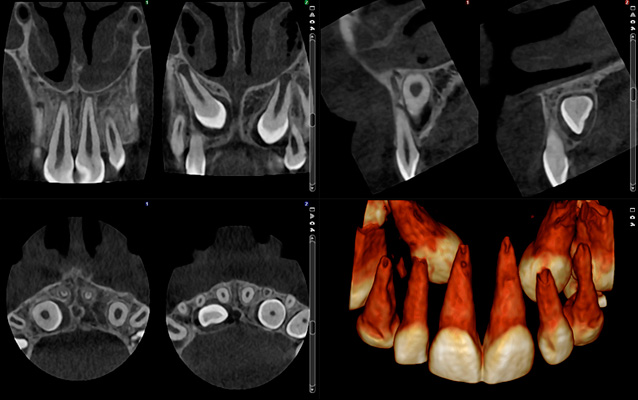

Planmeca ProMax 3D® – это серия аппаратов, состоящая исключительно из аппаратов “все-в-одном”. Три различных типа трехмерной визуализации, а также панорамная, цефалометрическая и внешняя съемка прикуса. Эти многофункциональные аппараты могут удовлетворить все Ваши потребности челюстно-лицевой визуализации.

Мы с гордостью представляем новый режим визуализации, который специально разработан для эндодонтических исследований. Новый режим съемки доступен на всех новых аппаратах Planmeca ProMax® 3D и обеспечивает идеальную визуализацию даже самых мелких анатомических деталей.

Эндодонтический режим съемки для аппаратов Planmeca ProMax® 3D

Благодаря интеллектуальной системе удаления шума Planmeca AINO™ и алгоритмам удаления артефактов Planmeca АРА™, получаемые изображения бесшумные и кристально чистые. Новый режим съемки идеально подходит для эндодонтии и других случаев, когда необходима визуализация маленьких анатомических деталей, таких как косточки уха.